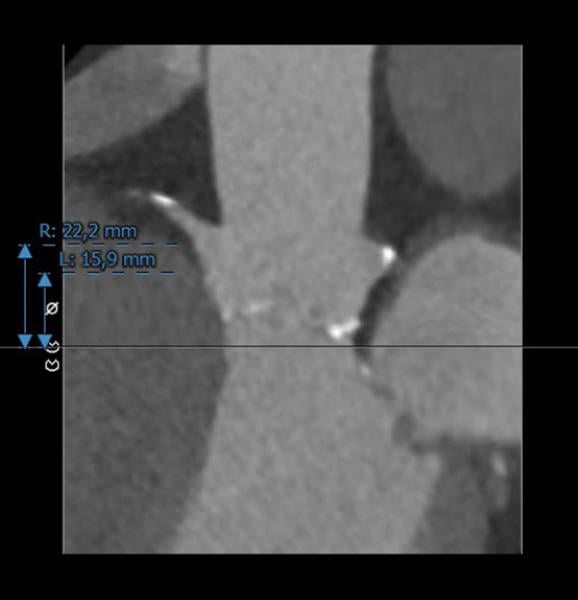

Case planning: CT

Annulus: 29.6 cm

LVOT: 32.2 cm

Moderate Ca2+, tricuspid

Sinus of Valsalva

LCA: 15.9 mm

RCA: 22.2 mm

Right

Left